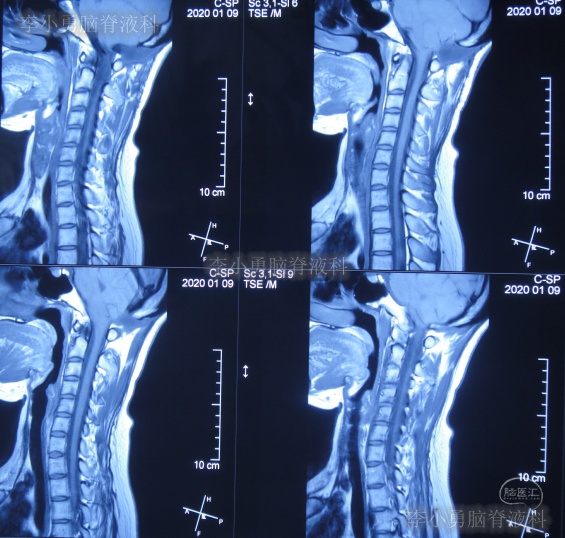

图-19:2020年1月9日

图-20:2020年1月9日颈部核磁